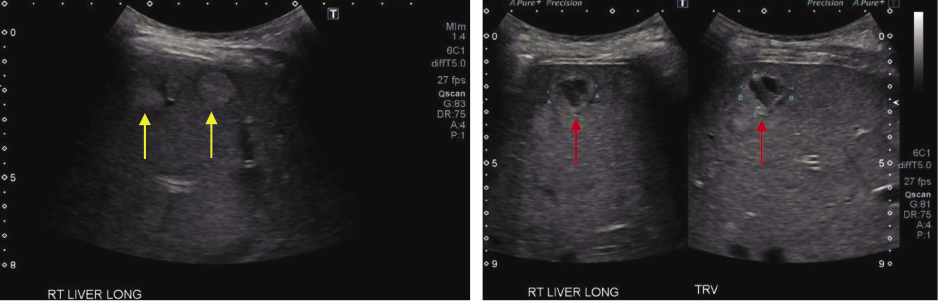

An abdominal ultrasound identified multiple complex cysts (red arrow) in the liver, including some with a target appearance (yellow arrow), and a dilated common bile duct (8.9 mm) (Figure 1).

Figure 1

Figure 1. Liver ultrasound demonstrating multiple focal lesion throughout both lobes and all segments of the liver, some echogenic with target appearance (left) some are complex cyst (right) concerning for metastasis.